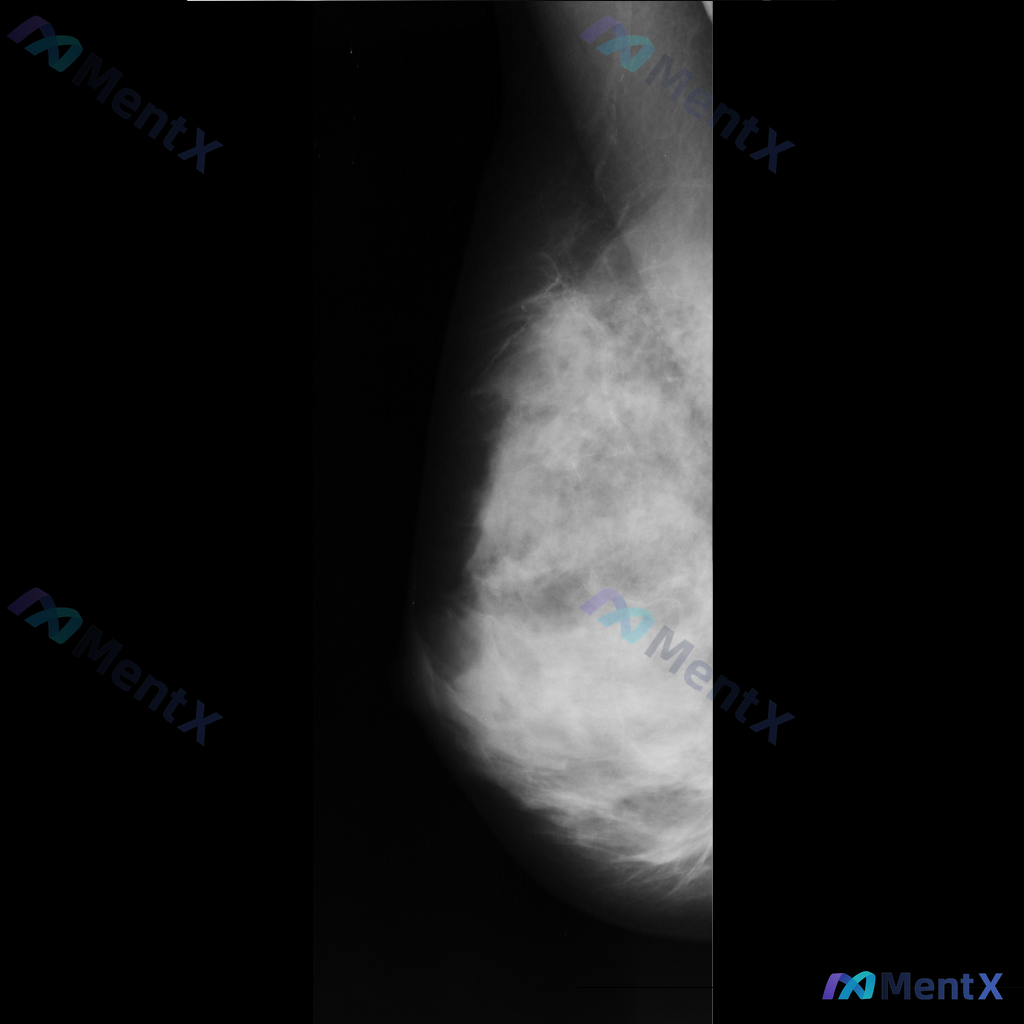

整理了一张乳腺钼靶影像的讨论资料,先和大家分享一下读片描述: 影像可见:不规则、高密度肿块/不对称致密影,伴有毛刺状边缘、结构扭曲和散在钙化。 目前考虑可能存在几种不同的异常方向,想先听听大家的第一反应——单看这组影像特征,你会先往哪种情况考虑? 也可以说说你最关注的是哪一点表现。

整理到一张乳腺钼靶的读片资料,想和大家一起讨论一下。 图像里能看到两处比较明确的异常: - 乳腺中下部有一个不规则、毛刺状的高密度肿块,周围还有结构扭曲的表现 - 乳腺上部还有一个类圆形的高密度肿块,形态相对规则一些 背景是不均匀致密型的乳腺组织。 单看这组图像表现,大家会优先往哪个方向考虑?

整理了一份乳腺钼靶影像病例,想和大家交流下判断思路。 影像表现: - 乳腺内可见不规则高密度肿块 - 肿块边缘呈毛刺状 - 伴有周围乳腺结构的扭曲和牵拉 目前可以考虑的方向有几个,想先问问大家:单看这份影像描述,你第一反应会更倾向哪一种情况?